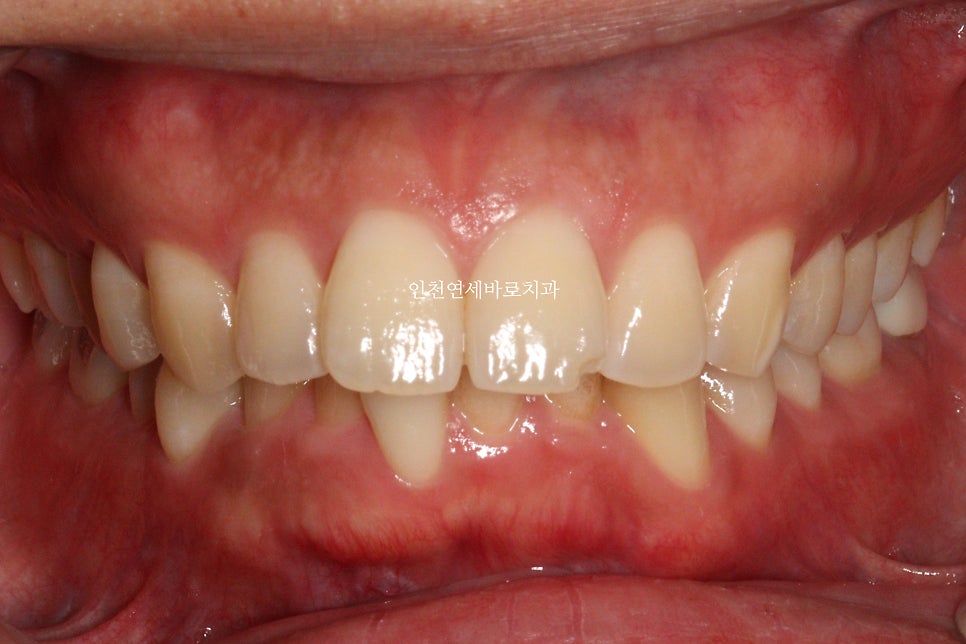

치료 전과 후의 비교입니다.

교합도 양호하게 마무리.

인비절라인은 교합이 맞지 않는다? 라는 말은 가스라이팅 당하신겁니다.

악궁의 확장을 통한 앞니의 후방이동도 최대한 이루어냈습니다.